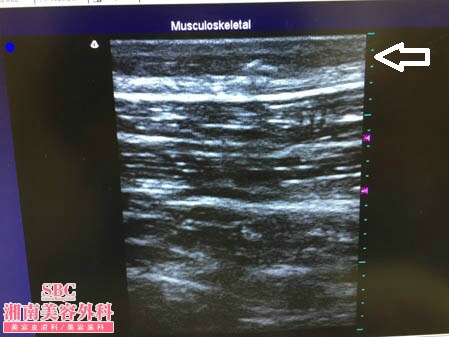

No.151291【脂肪吸引】YouTube手術関連動画掲載数・世界第一位! あの有名な根こそぎ竹田先生の劇的ビフォーアフター!〜社会人になってストレス太りしてしまったのを脂肪吸引で解消する!右太もも術中3Dタッチビュー〜

3Dタッチビューで皮下脂肪層の変化から

見ておきましょう。

3Dタッチビューで目で確認して

皮下脂肪層に取り残しや取りムラがないことが

分かった状態で手術を終了しますので

確実な結果を患者様にこの時点でお約束できます。